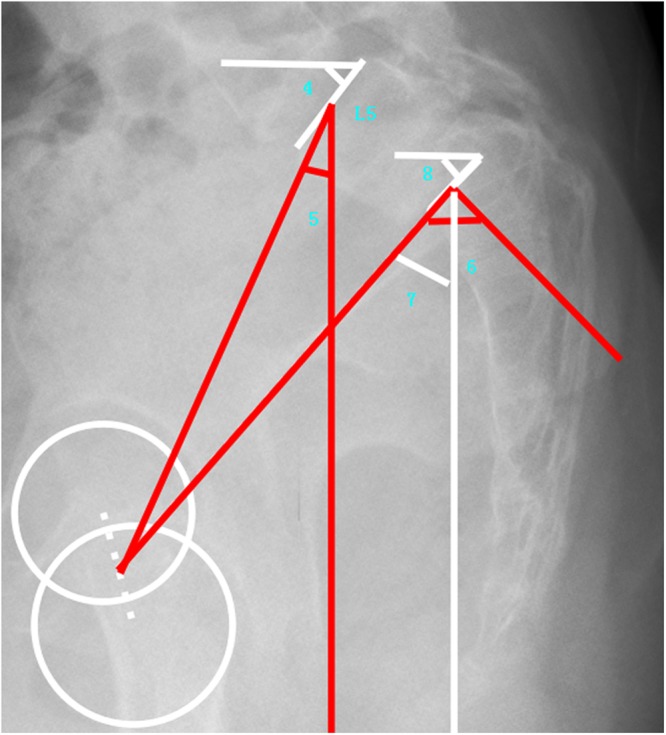

Sagittal lumbosacral parameters: SS, PT, PI, L5 Slope(the angle between a horizontal line and the superior end plate of L5), and L5I (L5 Incidence, the angle between the vertical line and the line connecting the center of the femoral heads axis to the center of the upper endplate of L523) (Fig. 3).

Figure 3.

Demonstrated sagittal lumbosacral parameters (4: L5 Slope, 5: L5 Incidence, 6: Pelvic Incidence, 7: Pelvic Tilt, and 8: Sacral Slope).